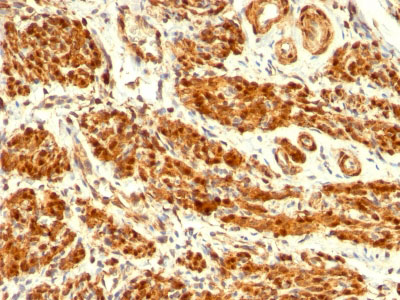

Formalin-fixed, paraffin-embedded human Uterus stained with Calponin-1 Monoclonal Antibody (CNN1/832).